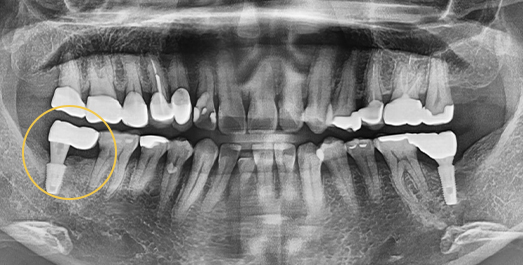

• BEFORE: 2021.11.02

• AFTER: 2022.01.19

타 치과에서 식립한 임플란트가 너무 멀리 잘못 심겨져 있어

올바른 위치로 재수술한 케이스입니다.